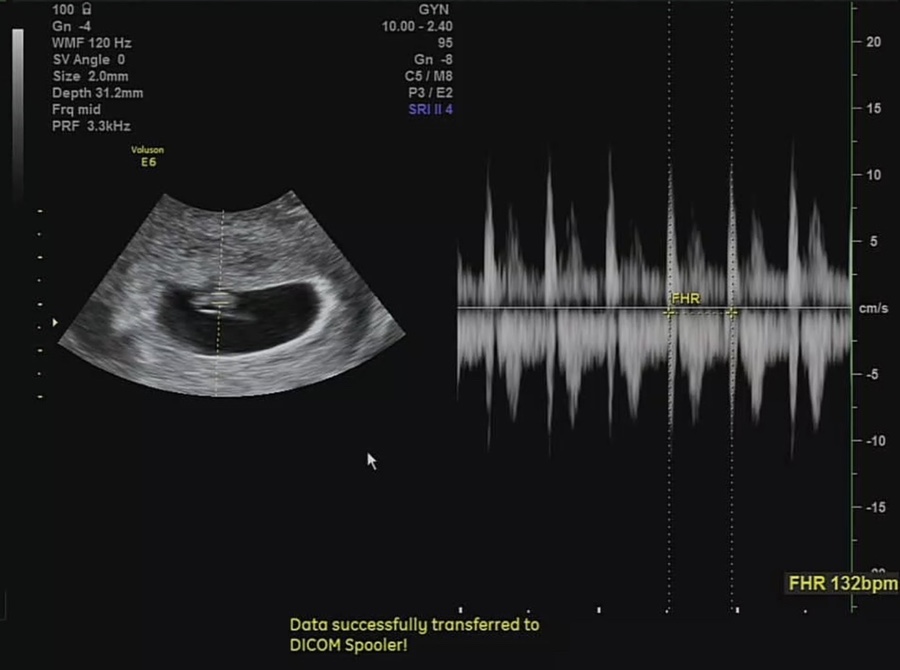

임신 7주 2일 심장 소리를 듣는다!

심장 소리도 듣고 왔습니다. ㅎㅎ 132bpm 아주 힘차요 ㅎㅎ